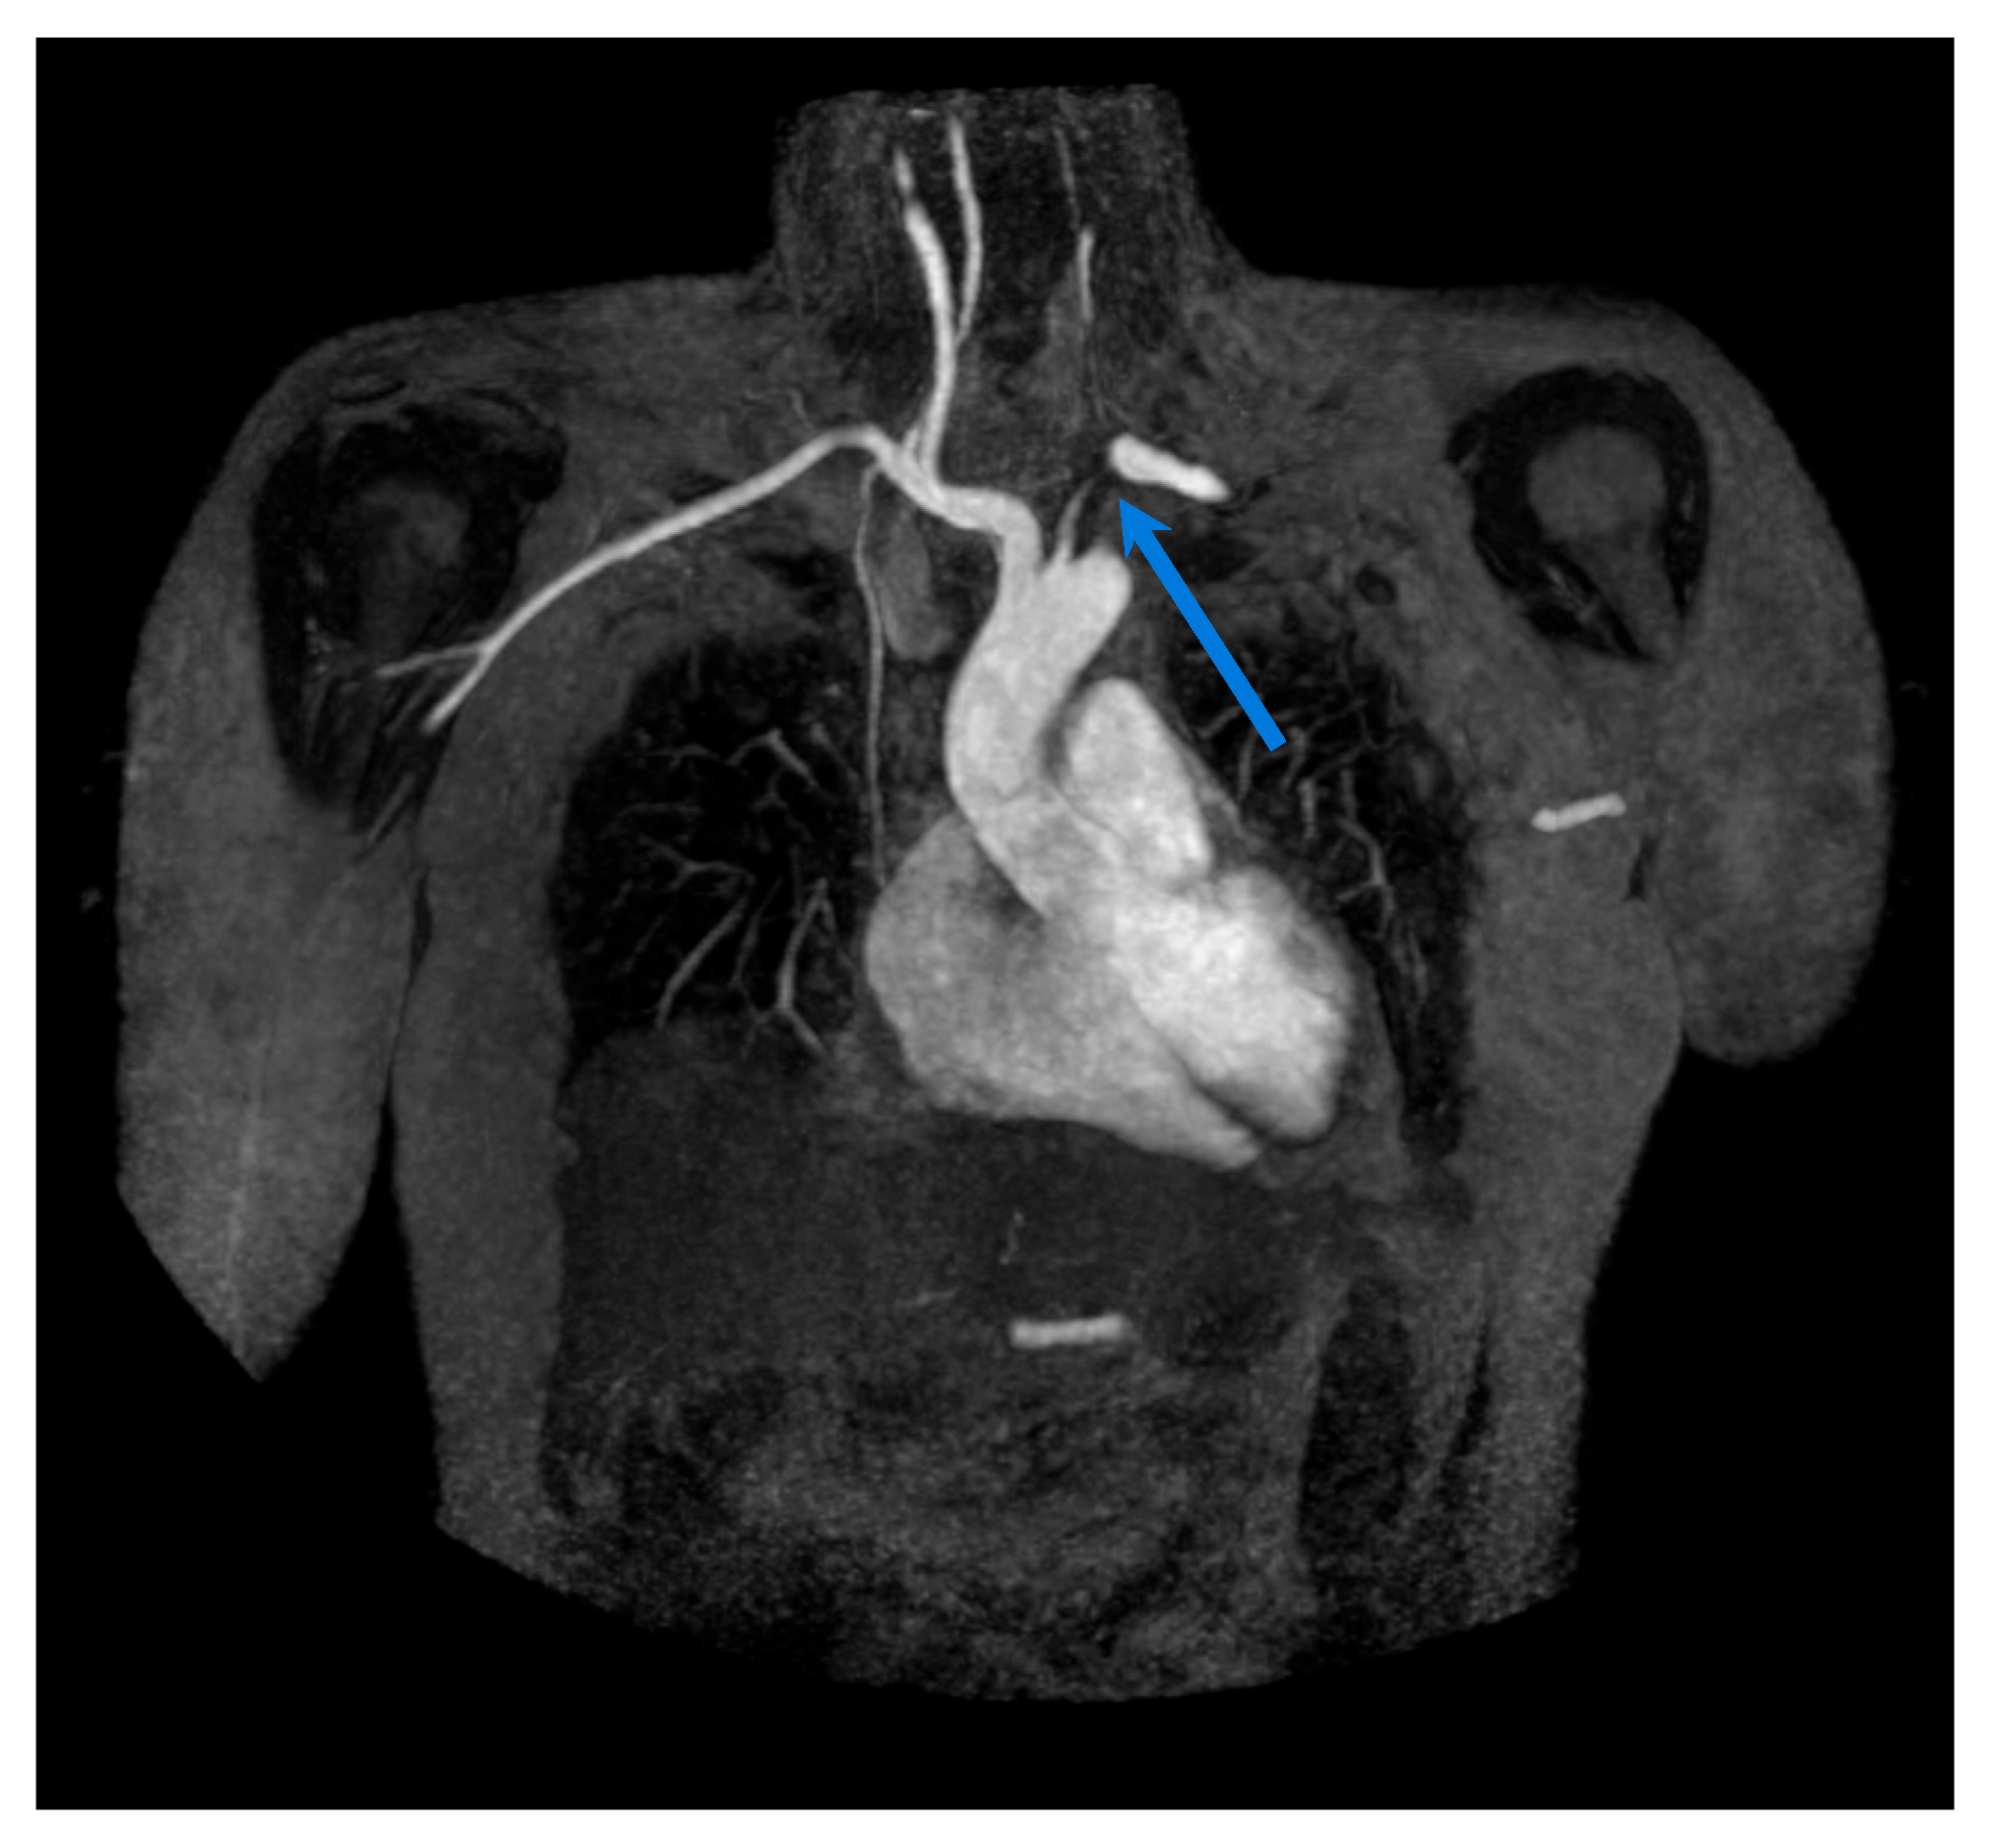

3. Magnetic Resonance Imaging

3.1. Giant Cell Arteritis

3.2. Takayasu Arteritis

- Reichenbach, S.; Adler, S.; Bonel, H.; Cullmann, J.L.; Kuchen, S.; Bütikofer, L.; Seitz, M.; Villiger, P.M. Magnetic resonance angiography in giant cell arteritis: Results of a randomized controlled trial of tocilizumab in giant cell arteritis. Rheumatology 2018, 57, 982–986. [Google Scholar] [CrossRef]

- Both, M.; Ahmadi-Simab, K.; Reuter, M.; Dourvos, O.; Fritzer, E.; Ullrich, S.; Gross, W.L.; Heller, M.; Bã¤Hre, M. MRI and FDG-PET in the assessment of inflammatory aortic arch syndrome in complicated courses of giant cell arteritis. Ann. Rheum. Dis. 2008, 67, 1030–1033. [Google Scholar] [CrossRef]

- Adler, S.; Sprecher, M.; Wermelinger, F.; Klink, T.; Bonel, H.; Villiger, P.M. Diagnostic value of contrast-enhanced magnetic resonance angiography in large-vessel vasculitis. Swiss Med. Wkly. 2017, 147, w14397. [Google Scholar] [CrossRef]

- Froehlich, M.; Guggenberger, K.V.; Vogt, M.; Mihatsch, P.W.; Torre, G.D.; A Werner, R.; Gernert, M.; Strunz, P.P.; Portegys, J.; Weng, A.M.; et al. MRVAS-introducing a standardized magnetic resonance scoring system for assessing the extent of inflammatory burden in giant cell arteritis. Rheumatol. Oxf. Engl. 2024, 63, 2781–2790. [Google Scholar] [CrossRef]

- Quinn, K.A.; Ahlman, M.A.; Malayeri, A.A.; Marko, J.; Civelek, A.C.; Rosenblum, J.S.; A Bagheri, A.; A Merkel, P.; Novakovich, E.; Grayson, P.C. Comparison of magnetic resonance angiography and 18F-fluorodeoxyglucose positron emission tomography in large-vessel vasculitis. Ann. Rheum. Dis. 2018, 77, 1165–1171. [Google Scholar] [CrossRef]

- Christ, L.; Bonel, H.M.; Cullmann, J.L.; Seitz, L.; Bütikofer, L.; Wagner, F.; Villiger, P.M. Magnetic resonance imaging to monitor disease activity in giant cell arteritis treated with ultra-short glucocorticoids and tocilizumab. Rheumatol. Oxf. Engl. 2025, 64, 2059–2067. [Google Scholar] [CrossRef]